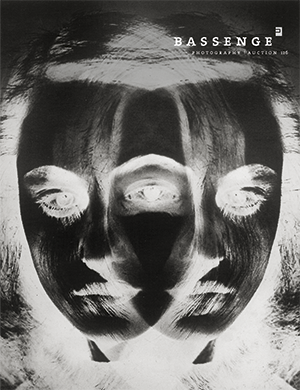

X-ray of a hand with a ring

Photographer unknown. X-ray of a hand with a ring. Circa 1910. Vintage collodion print. 22,5 x 17 cm. Mounted to original board with gilt-ruled outline.

This striking early radiographic image captures the skeletal structure of a hand adorned with a ring, exemplifying the fascination with X-ray technology following its discovery by Wilhelm Röntgen in 1895. Likely made for scientific or medical demonstration, the print highlights the translucency of flesh and the opacity of metal in dramatic contrast. – Buckling from mounting, a few small spots and areas of discoloration, liquid staining in upper and lower corners, slightly faded.